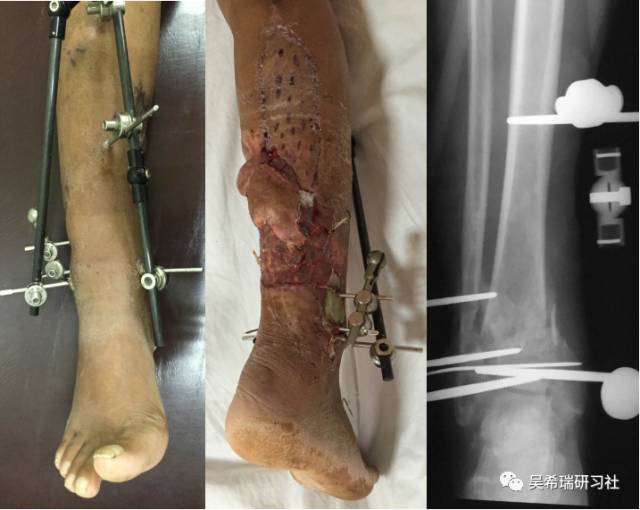

双下肢车祸外伤保肢的理由是足底皮肤好

TIPS:清创&盐水冲洗(不用双氧水)VSD骨水泥技术&开放植骨单边外固定架(下胫腓联合固定)早期下地 生理应力 + 机械应力游离植皮 / 不用皮瓣清创时游离皮质骨去除胫跖骨牵引技术防治&纠正足下垂